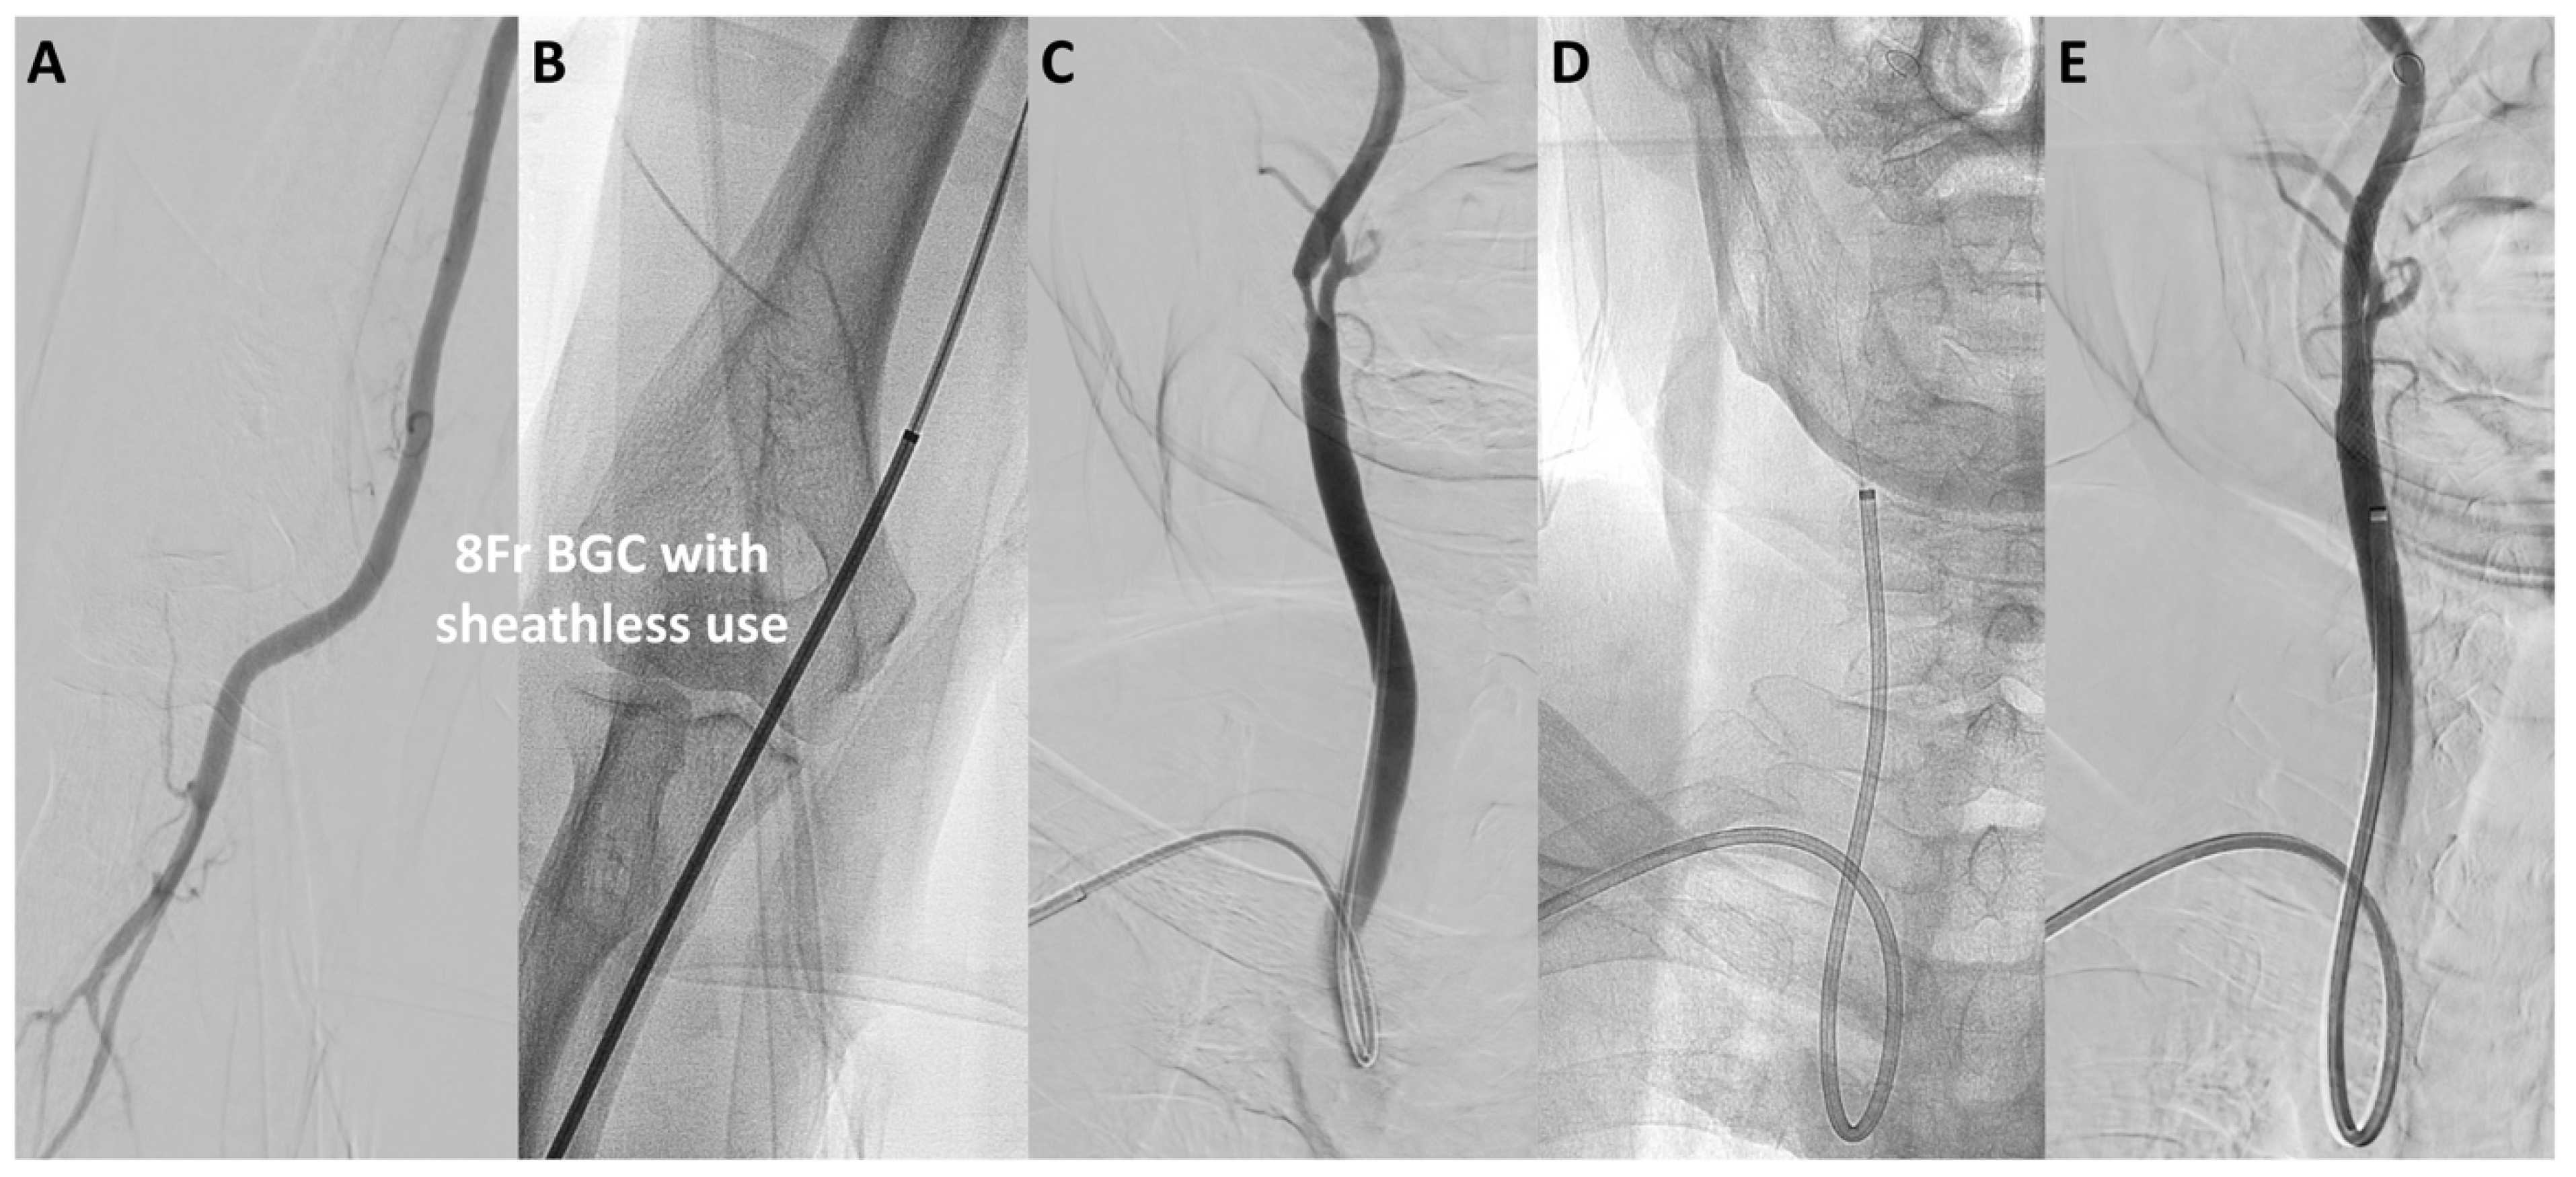

4.4. Sheathless BGC Use in TRA

- Koge, J.; Iwata, T.; Hashimoto, T.; Mizuta, S.; Nakamura, Y.; Tanaka, E.; Kawajiri, M.; Matsumoto, S.-I.; Yamada, T. Carotid artery stenting with proximal embolic protection via the transbrachial approach: Sheathless navigation of a 9-F balloon-guiding catheter. Neuroradiology 2018, 60, 1097–1101. [Google Scholar] [CrossRef]

- Hanaoka, Y.; Koyama, J.-I.; Kiuchi, T.; Kamiya, K.; Kuwabara, H.; Kamijo, T.; Horiuchi, T.; Hongo, K. Proximal balloon protection during carotid artery stenting via the transradial approach. J. Neuroendovascular. Ther. 2018, 12, 520–526. [Google Scholar] [CrossRef]

- Harada, K.; Fujimura, H.; Kajihara, M.; Arakawa, K. Carotid artery stenting using a 7 French Optimo balloon guide catheter combined with a distal filter. Interv. Neuroradiol. 2023, 15910199231162492. [Google Scholar] [CrossRef]

| Sheathless 8Fr BGC (2.7) | 0% (0) | 70% (30) | |